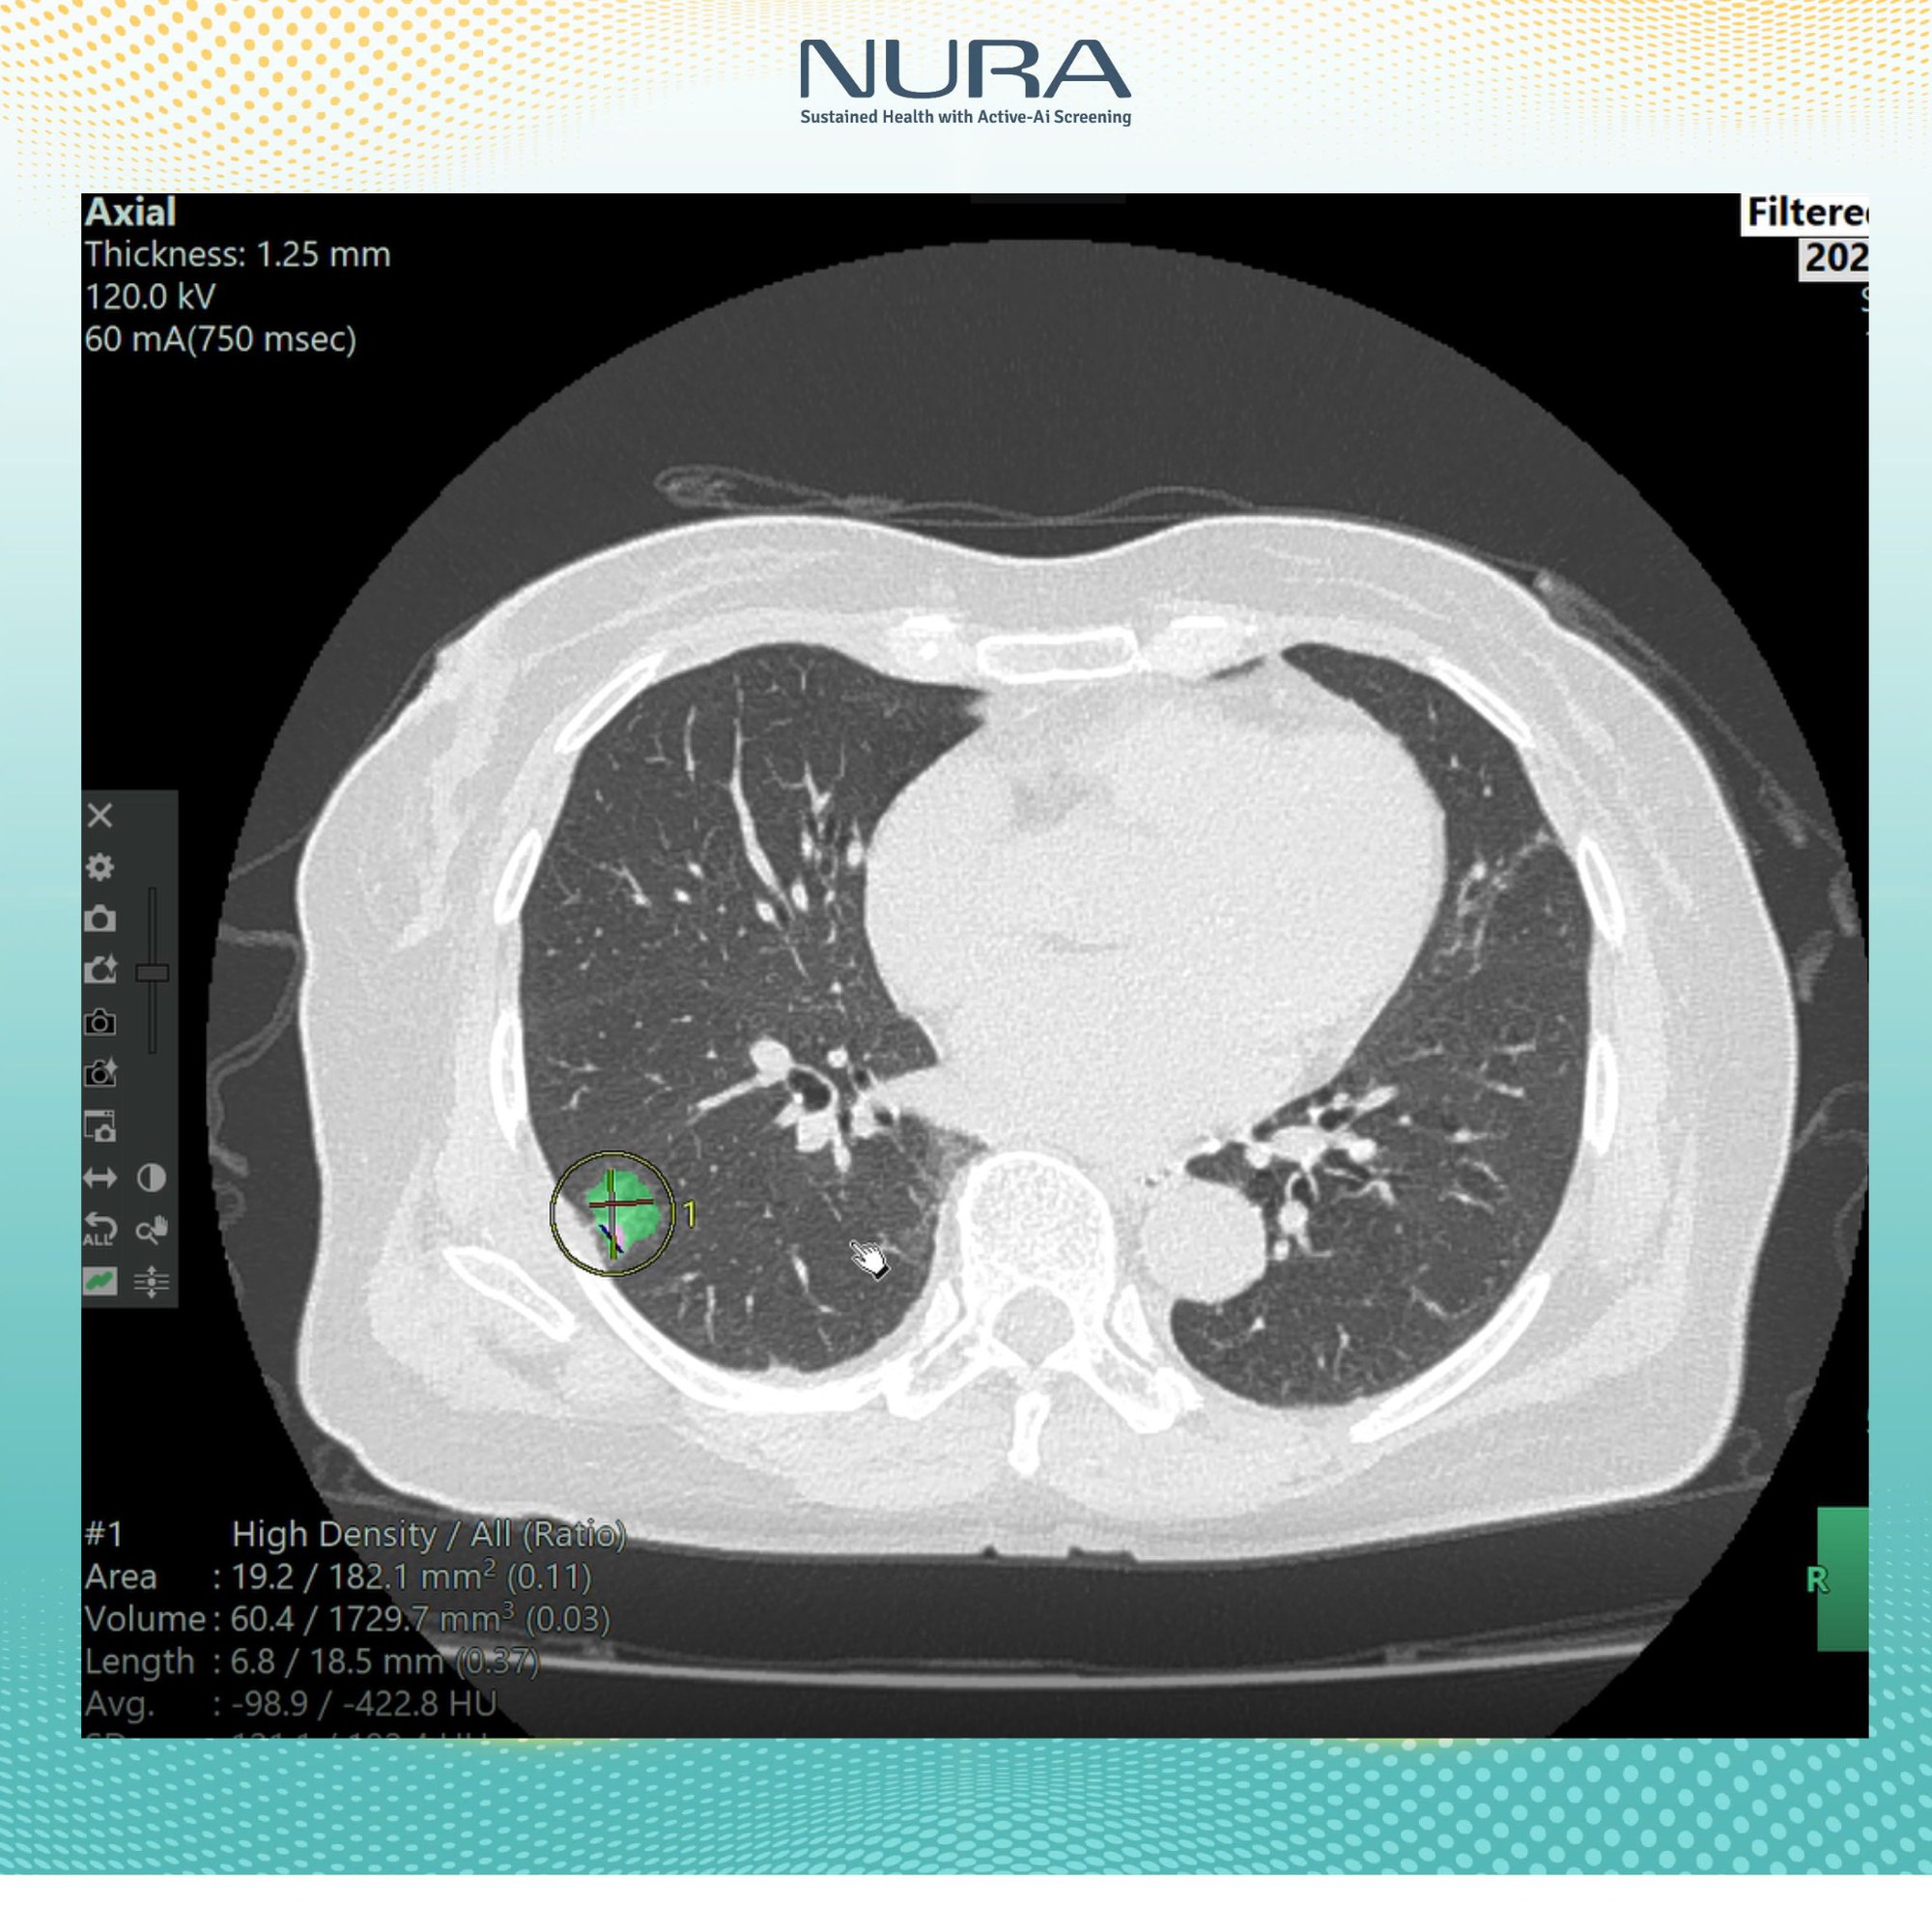

“Công nghệ AI của NURA không chỉ đơn thuần là công cụ hỗ trợ, mà còn đóng vai trò quan trọng trong quy trình phân tích và nhận diện hình ảnh. Bằng cách thu thập và xử lý dữ liệu hình ảnh y khoa từ hơn 400 triệu ca bệnh được Fujifilm Nhật Bản lưu trữ trong suốt 10 năm, AI có thể nhận diện sớm các tổn thương bất thường – từ những nốt nhỏ nhất, kích thước từ 1mm trở lên.

Tại NURA, công nghệ AI được xây từ 400 triệu bộ dữ liệu hình ảnh và tích hợp trong hệ thống tầm soát công nghệ cao, cho phép lưu trữ và phân tích dữ liệu hình ảnh rõ nét, vượt trội so với phương pháp chụp cắt lớp truyền thống”, Đại diện NURA chia sẻ với báo chí.

Chỉ sau vài phút, kết quả sẽ được gửi về dưới dạng các hình ảnh cắt lớp chi tiết. Những lát cắt này cho phép bác sĩ phát hiện các tổn thương có kích thước từ 1mm, giúp việc chẩn đoán trở nên chính xác và nhanh chóng hơn rất nhiều.

- Về tính chính xác: AI không chỉ giúp phát hiện tổn thương từ rất sớm, mà còn tự động đo kích thước từng nốt nghi ngờ, đếm số lượng, đánh giá mức độ nguy cơ và hỗ trợ bác sĩ trong việc đưa ra quyết định chuyên sâu.